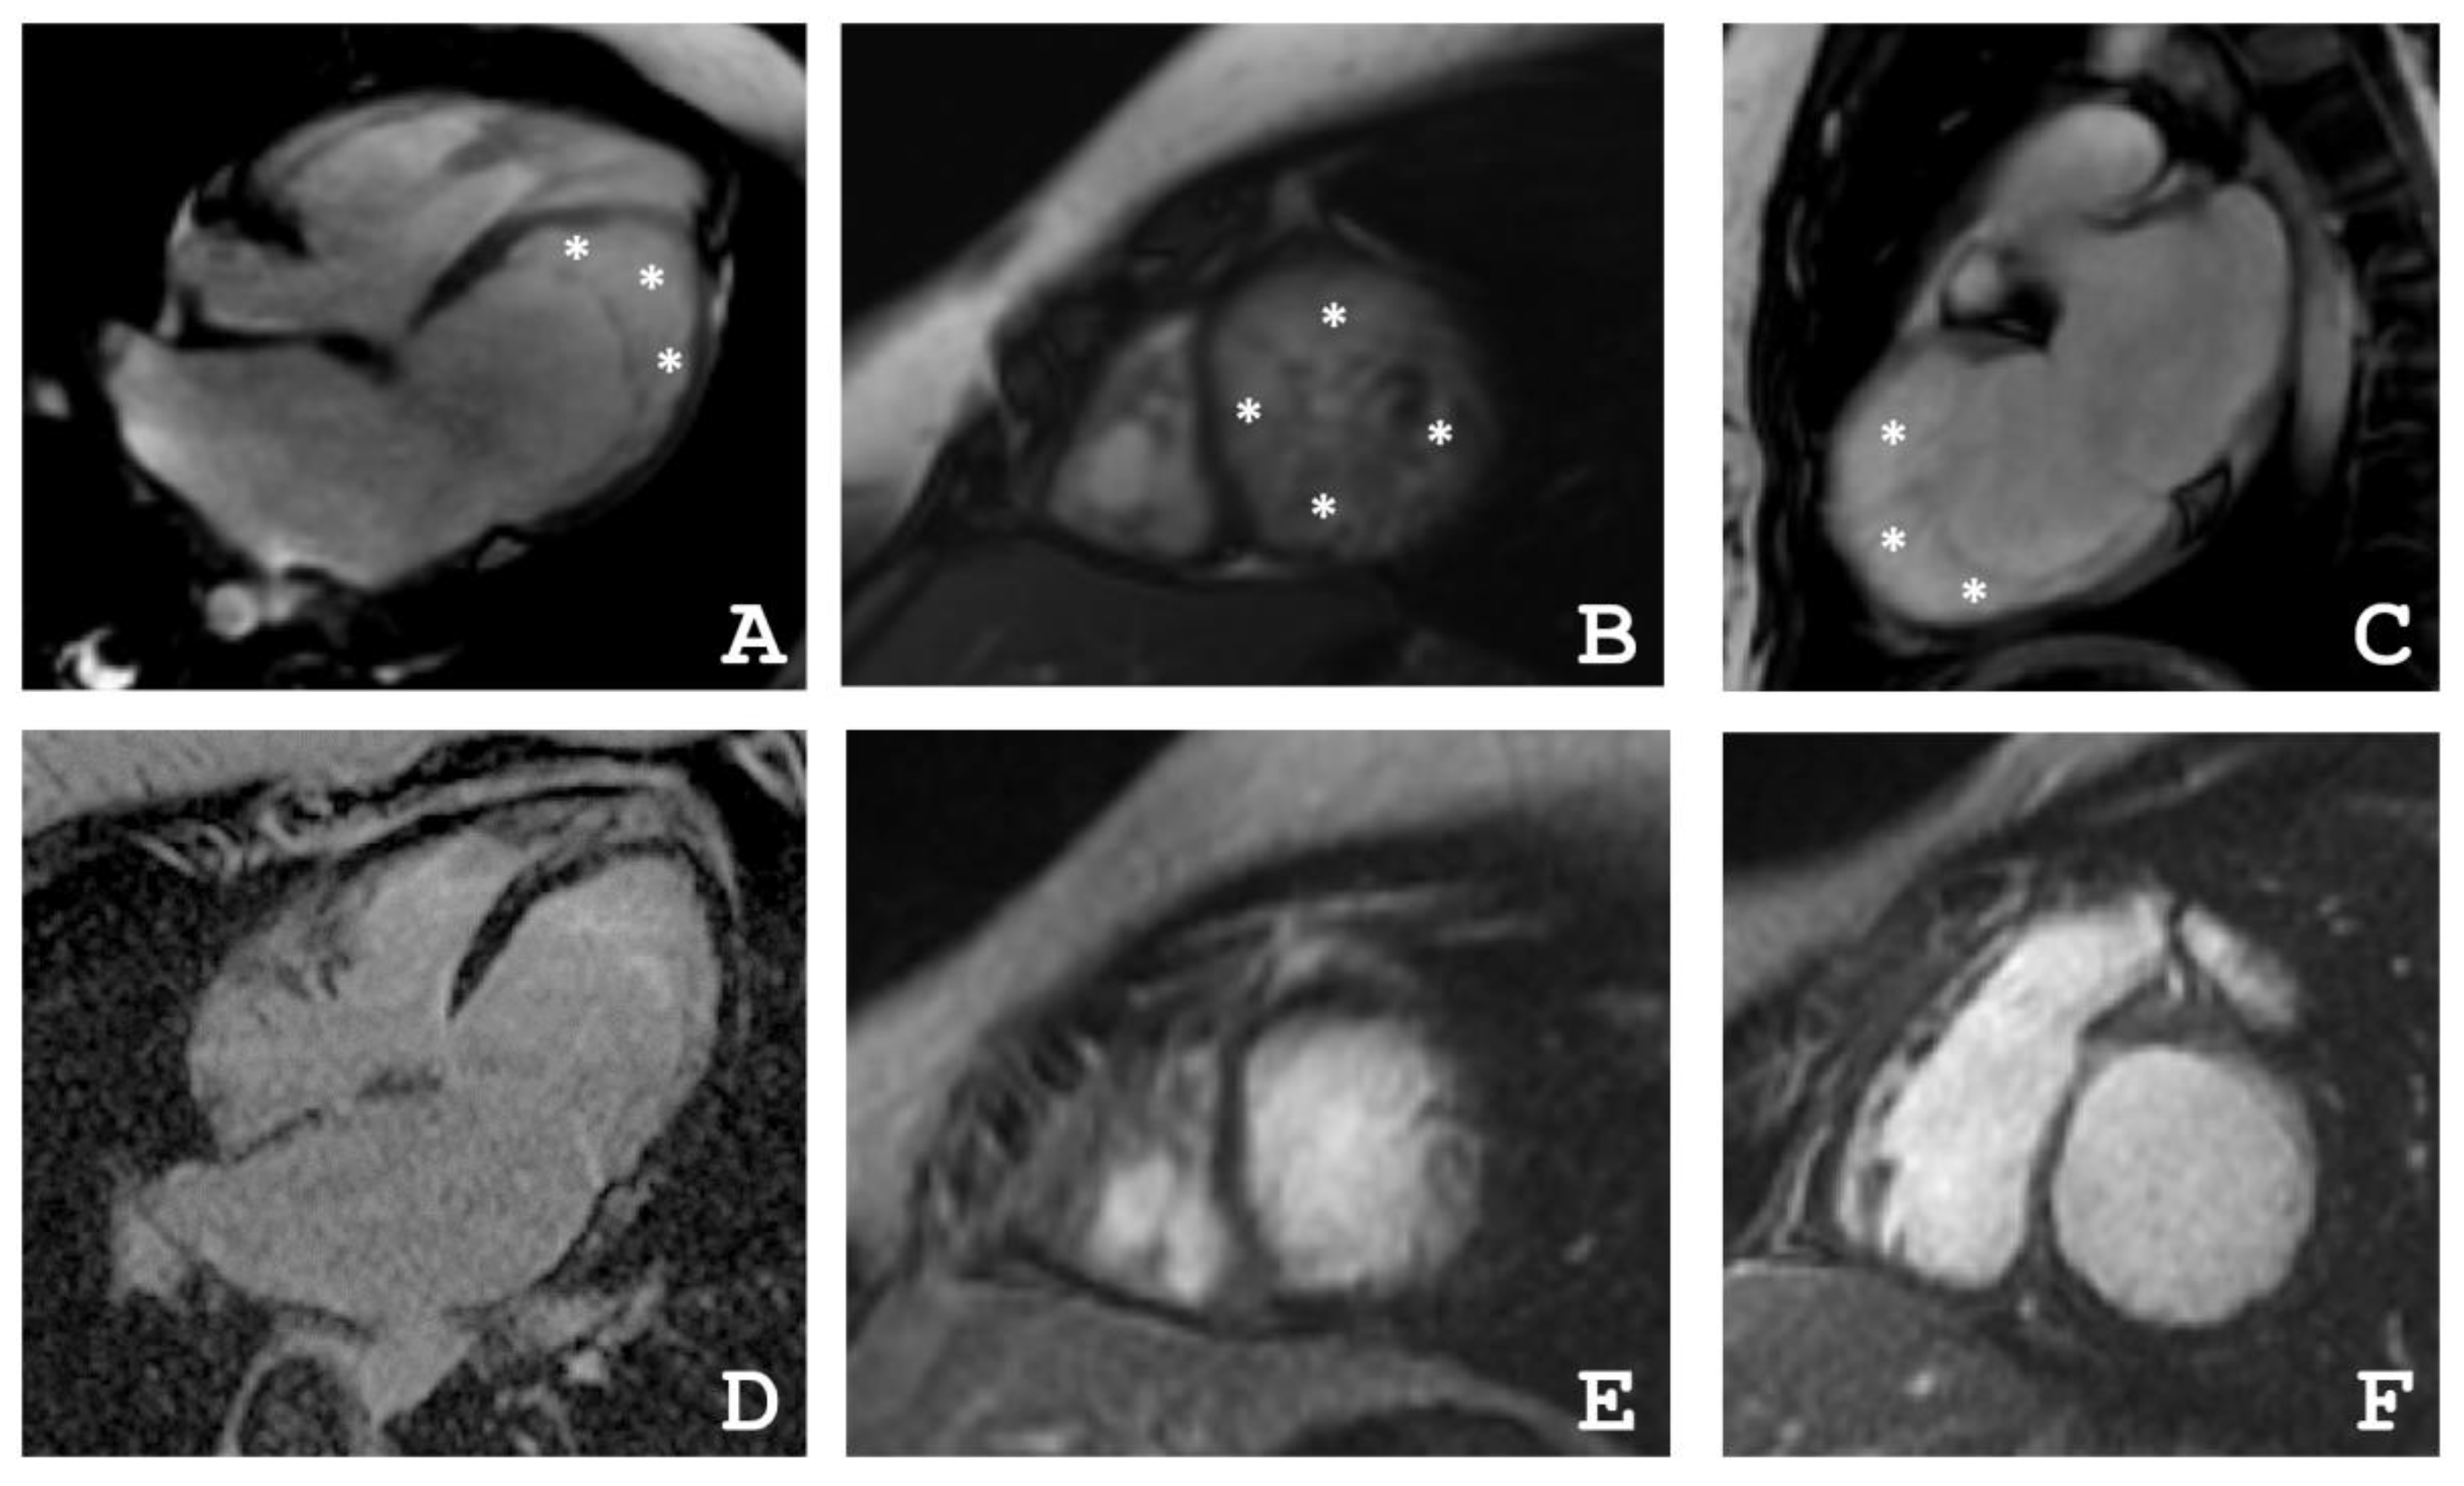

2.1. Clinical Investigations

4.2. Cardiac Magnetic Resonance Imaging